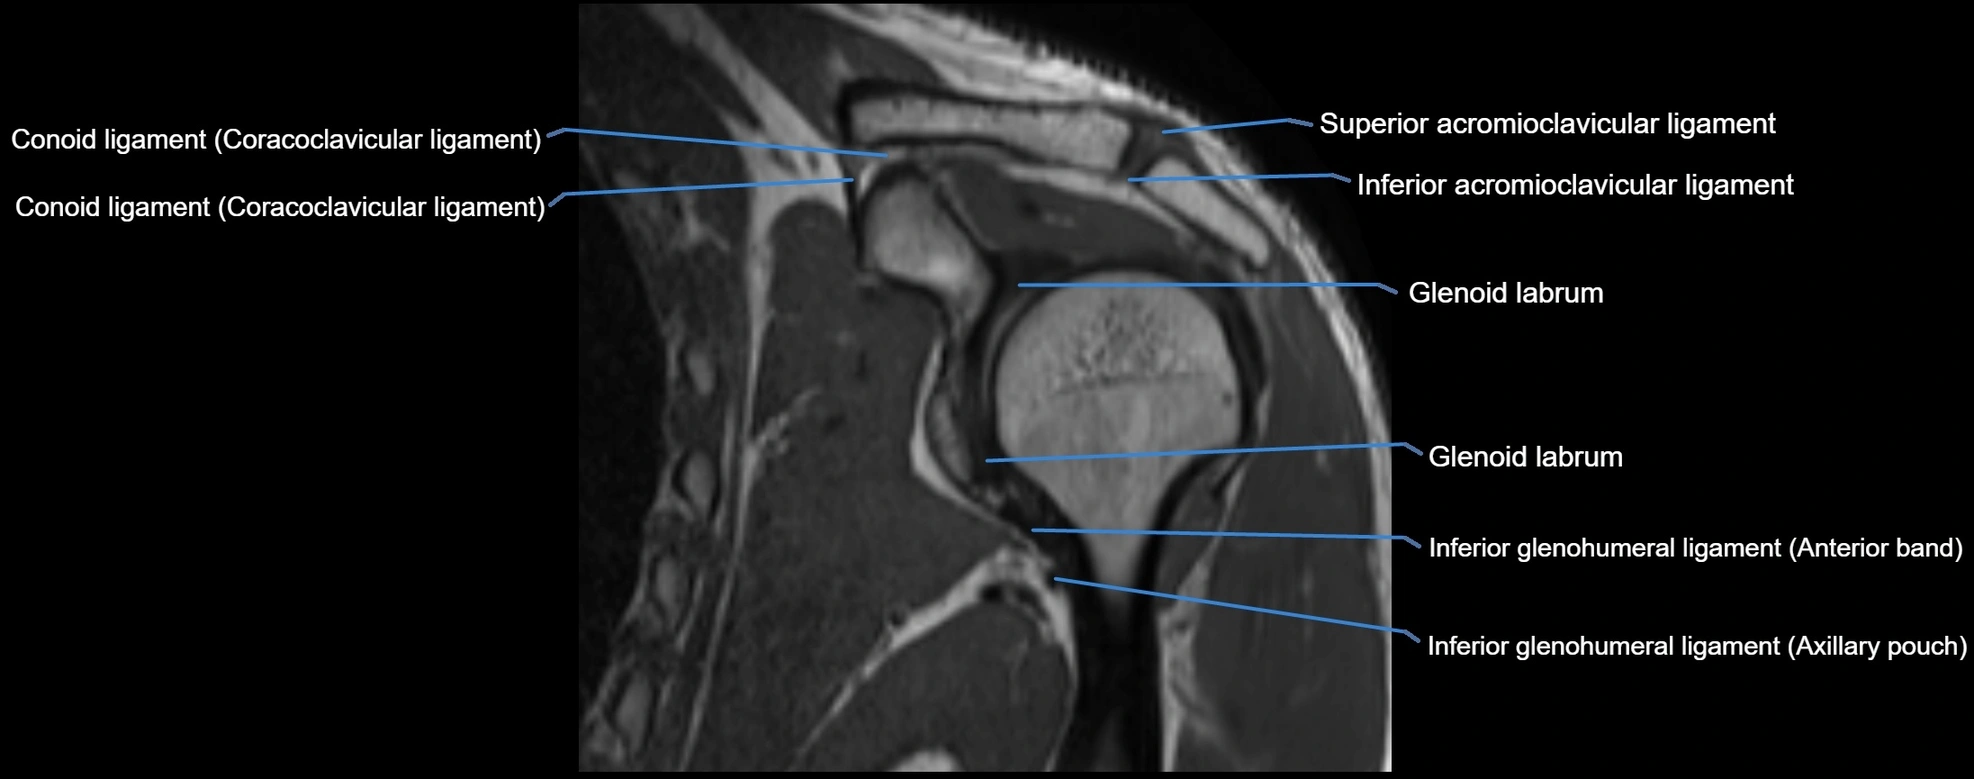

MRI images

image